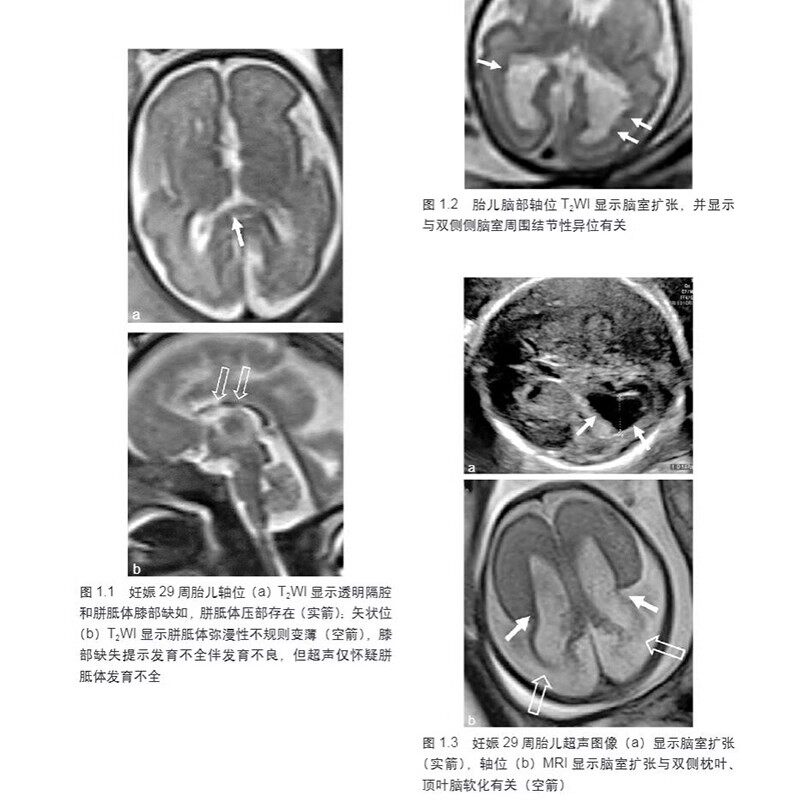

本书由国际著名胎儿磁共振成像(MRI)专家R.拉杰斯瓦拉主编,旨在全面介绍胎儿MRI临床应用的相关情况。全书对胎儿MRI检查安全性、适应证、禁忌证、检查技术、胎儿各系统MRI正常解剖及异常发育进行了全面细致的总结,并以简洁明了的方式介绍了胎儿各系统发育的基础知识,对胎儿在发育中各种异常征象配以大量插图,包括异常发育示意图、典型MRI图像,且在必要的位置增加了超声图像及产后照片做对比,强调了MRI相对于超声的优势,并提供了精准的注释。